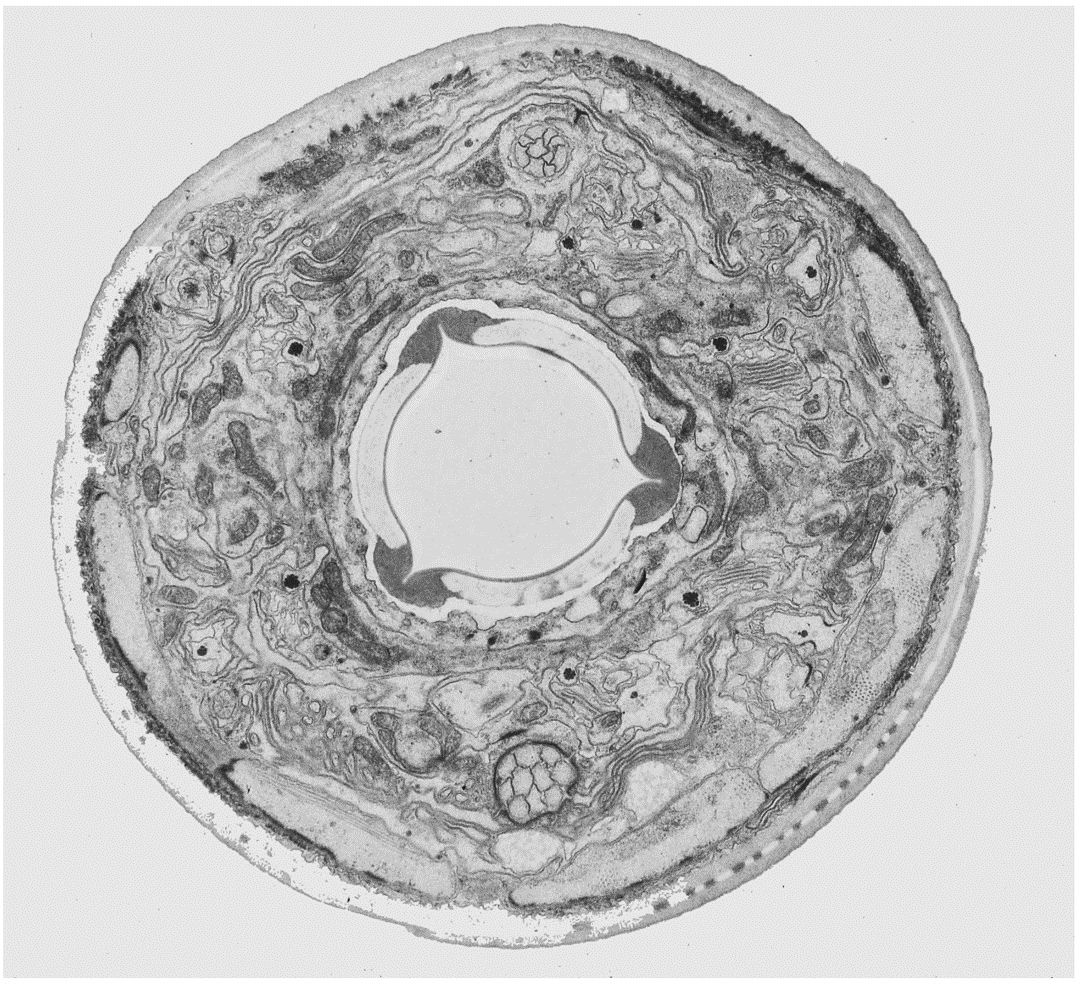

2. Eletrônico

1. Caro e complexo, porém,com altíssima resolução

1. Célula vista por microscópio eletrônico